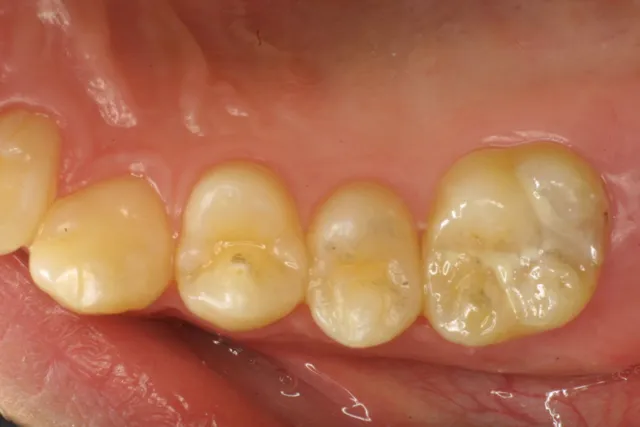

【1】奥歯の溝に出来たムシ歯・黒っぽく変色した部分ばムシ歯です

【1】奥歯の溝に出来たムシ歯